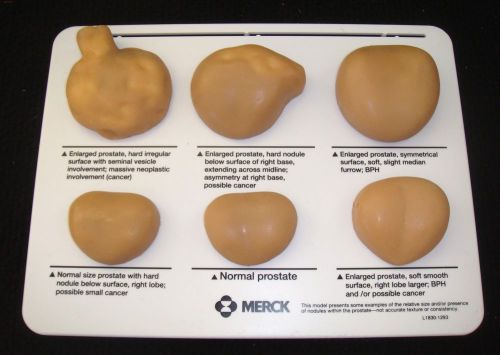

Prostate Anatomical Model for Patient Education in box